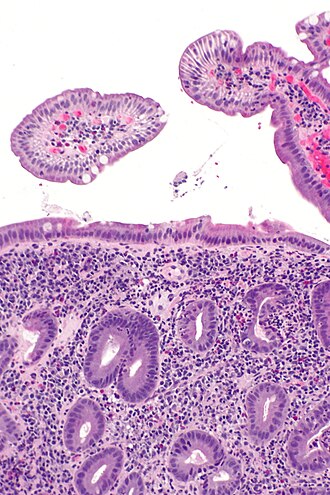

Acute duodenitis. H&E stain. | |

| LM | neutrophils - "found without searching", eosinophils - "found without searching", plasma cells (increased), intraepithelial lymphocytes |

The sections show small bowel mucosa with intraepithelial neutrophils. The epithelium shows nuclear hyperchromasia, pseudostratification and nuclear enlargement; however, it matures toward the surface (reactive changes of the epithelium).

Brunner's glands are found focally in the lamina propria. Gastric foveolar-type epithelium is identified. Lamina propria plasma cells are abundant.